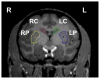

A single unilateral intracarotid infusion of 1-methyl-4-phenyl-1,2,3,6-tetrahydropyridine (MPTP) into non-human primates causes injury to the nigrostriatal pathway including nigral cell bodies, axons and striatal terminal fields. In this model, motor parkinsonism correlates well with the loss of nigral dopaminergic cell bodies but only correlates with in vitro measures of nigrostriatal terminal fields when nigral cell loss does not exceed 50%. The goals of this study are to determine the relationship of motor parkinsonism with the degree of injury to nigrostriatal axons, as reflected by in vitro fiber length density measures, and compare in vivo with in vitro measures of striatal terminal fields. We determined axon integrity by measuring fiber length density with tyrosine hydroxylase (TH) immunohistology and dopamine transporter (DAT) density with DAT immunohistology. We then calculated the terminal arbor size and compared these measures with previously published data of quantified in vivo positron emission tomography (PET) measures of presynaptic dopaminergic neurons, autoradiographic measures of DAT and vesicular monoamine transporter type 2 (VMAT2), striatal dopamine, nigral cell counts, and parkinsonian motor ratings in the same animals. Our data demonstrate that in vivo and in vitro measures of striatal terminal fields correlate with each other regardless of the method of measurement. PET-based in vivo striatal measures accurately reflect in vitro measures of DAT and VMAT2. Terminal arbor size and other terminal field measures correlate with nigral TH immunoreactive (TH-ir) cell counts only when nigral TH-ir cell loss does not exceed 50%. Fiber length density was the only striatal measure that linearly correlated with motor ratings (Spearman: r=-0.81, p<0.001, n=16).